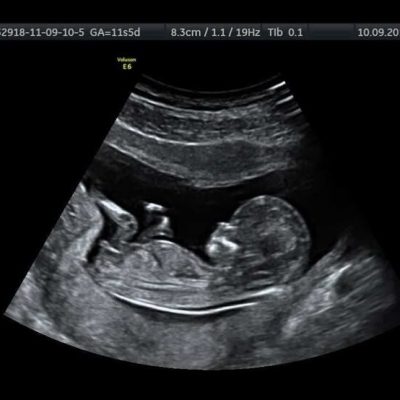

Sonography

Scanning support helps observe reproductive wellness and therapy movement. It serves as a regular element of fertility observation delivered by an IVF Center in Pimpri-chinchwad for individuals visiting from surrounding Pimpri locations.